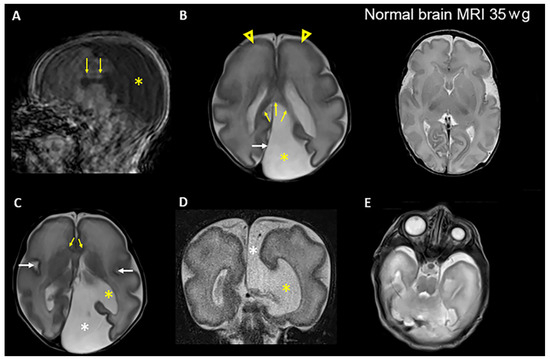

Figure 2.

Brain MRI images of patient 1 in the postnatal period at approximately 35 weeks gestational age demonstrate multiple congenital anomalies. (A) Sagittal T1-weighted image shows the presence of the corpus callosum, which is not properly developed (arrows). The posterior portion (the splenuim) is located further anterior than normal. CSF fills most of the posterior supratentorial compartment (asterisk). Note motion artifacts in the basal regions of the brain. (B) Left: Axial T2-weighted image shows an expansion of the left supratentorial cranial cavity (interhemispheric cyst) filled with CSF (asterisk) in the parietooccipital region of the left hemisphere. The posterior falx cerebri (white arrow) is shifted toward the right hemisphere. The splenium of the corpus callosum is visible (yellow arrows). There is primitive gyrosulcal patterning, more prominent in the frontal lobes (arrowheads), consistent with 28–29 weeks of gestation. Right: Axial T2-weighted image shows normal gyrus and sulcus formation at 35 weeks of gestation (wg). (C) Axial T2-weighted image shows the interhemispheric cyst (white asterisk) communicating with the enlarged left lateral ventricle (yellow asterisk). The genu of the corpus callosum is visible (yellow arrows). The sylvian fissures (white arrows) appear underdeveloped in both hemispheres. (D) Coronal T2- weighted image shows the communication of the CSF space (interhemispheric cyst) (white asterisk) with the lateral ventricle (yellow asterisk) on the left side through a broad parenchymal defect in the medial temporoparietal region. (E) Axial T2-weighted image shows pronounced left microphthalmia, without detectable lens.